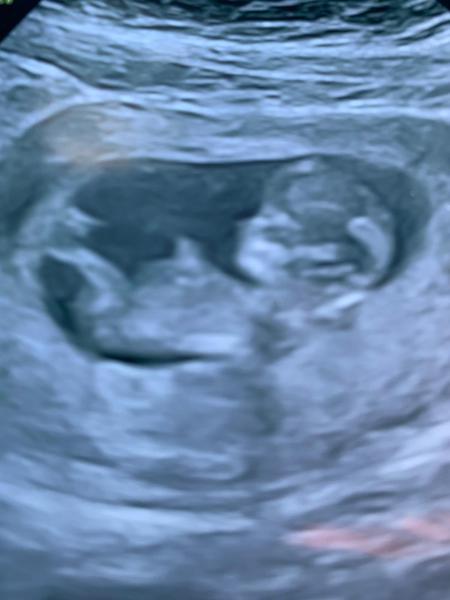

Had my private scan today and everything was perfect measuring at 11+3 and baby was moving around loads so I feel hugely relieved and just grateful for the lack of symptoms just goes to show I was worrying about nothing but think we are all guilty of that! X

@megan81088 congratulations on your scan! Baby looks amazing, so much like a real little baby! I can't wait for mine... it's in a week and a half, and I'll be 12+2. Eeee. Very excited, and a little nervous.

Wow amazing scans. So crazy how much it actually looks like a baby! So please for you. I am wondering in your 12 week scan, do you hear the heartbeat? Xxx